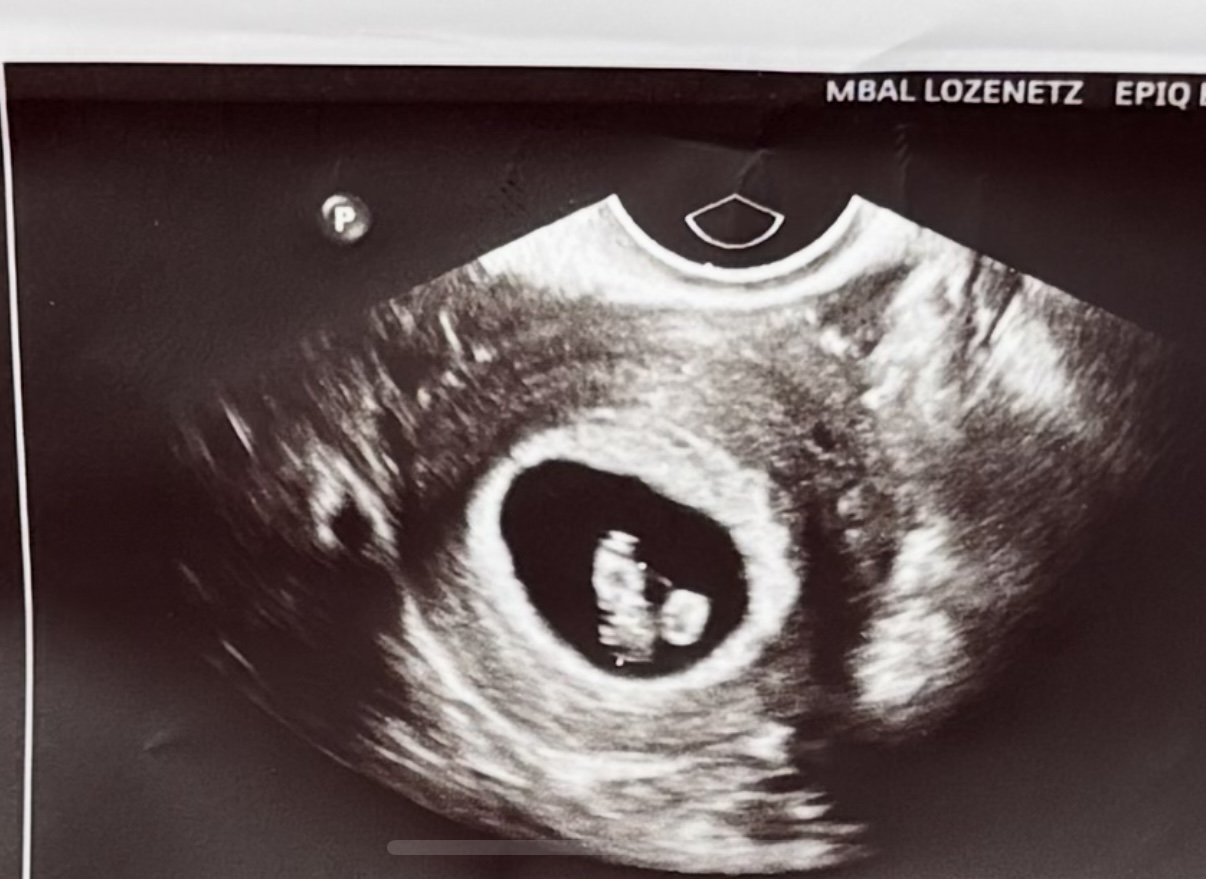

Здравейте. 7 седмица и 5 ден съм. Може ли да ми кажете от опита ви от ваши ехографи на смимката какво е кръгчето и телцето? Понеже не ми поясни доктора.

Не съм медицинско лице, но на един от първите прегледи доктора каза, че в началото се формира плоден сак с ембрион и жълто мехурче, което изчезва в един момент.

Това трябва да са ембрион и жълто тяло.